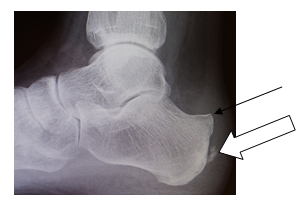

Achillessehnensporn

Der Achillessehnensporn wird auch als hinterer (=dorsaler) Fersensporn bezeichnet und ist als ein Zeichen der chronischen Überlastung zu sehen. Der knöcherne Sporn wächst direkt in die Achillessehne ein und verursacht dort unter Belastung und bei engem Schuhwerk Schmerzen. Durch die Reizung der Achillessehne treten die Schmerzen jedoch oft auch in Ruhe auf. Meist wird die Achillessehne zusätzlich noch durch eine sogenannte Haglund Exostose bedrängt. Diese liegt etwas weiter oberhalb und führt dazu, dass die Achillessehne über eine knöcherne Kante des Fersenbeins gleitet. Eine schmerzhafte Entzündung eines Schleimbeutels schränkt dann zusätzlich das Gehen deutlich ein.

Auch wenn durch Physiotherapie die Beschwerden etwas gemindert werden können, werden die Patienten selten dadurch schmerzfrei. Grund dafür ist der knöcherne Sporn in der Sehne, der früher oder später wieder zu Schmerzen führt. Dann sollte der Sporn operativ abgetragen werden. Dazu muss die Achillessehne von dem Fersenbein gelöst werden, damit der Sporn aus der Sehne entfernt werden kann. Ebenfalls wird der knöcherne Überstand der Haglund Exostose abgetragen. Anschließend wird die Sehne mit speziellen sog. Ankersystemen am Knochen wieder befestigt.